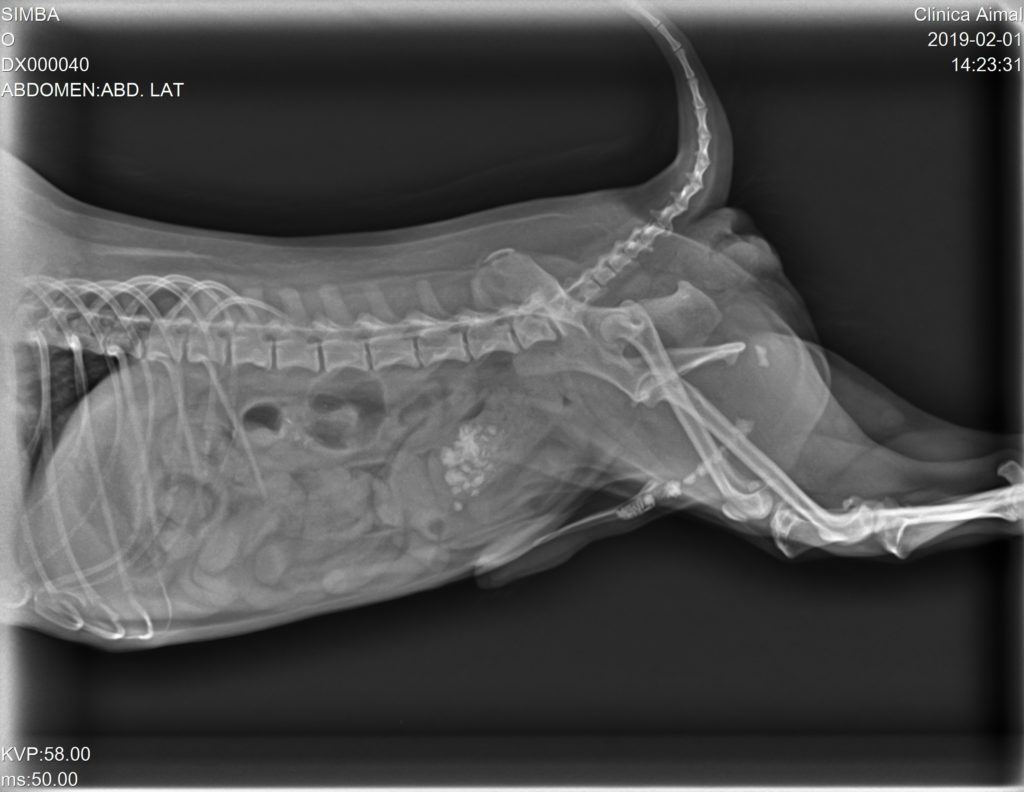

En la Rx pudimos observar gran cantidad de urolitos en la vejiga de la orina y uretra, depositándose en la parte más caudal del hueso peneano provocando una obstrucción incompleta:

Se sonda al animal para arrastrar mediante sonda y suero fisiológico a los cálculos de nuevo a la vejiga de la orina. Una vez realizado esto y contrastado mediante Rx, se pone tratamiento antibiótico, antiinflamatorio y se les cita para cirugía, en la cual se realizará una cistotomía y así retirar todos los cálculos.

Tres días más tarde realizamos otra Radiografía de control y nos percatamos que algunos urolitos vuelven a estar depositados a lo largo de la uretra, por lo que antes de la cistotomía debemos realizar un sondaje para arrastrar los urolitos de nuevo a vejiga para poder retirarlos mediante la cistotomía.